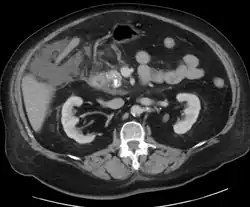

Acute exudative pancreatitis on CT scan -

Calcified pancreatic duct stones with some free intra-abdominal fluid